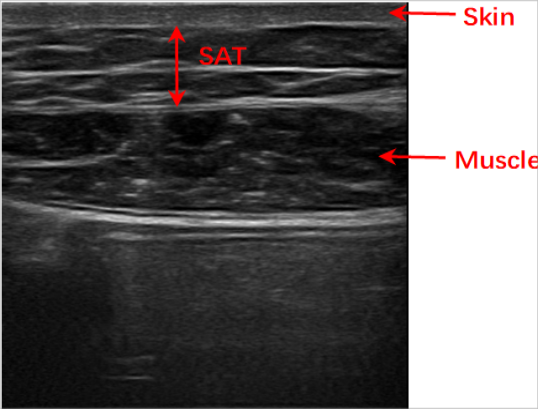

定义 SAT 的直线上边界(皮肤—脂肪层)和二次曲线下边界(脂肪—肌肉层)

从二维规化图像,建立 CNN 回归模型以决定 SAT 的上边界和下边界

皮下脂肪含量(Subcutaneous Adipose Tissue,SAT)是体脂肪测试的重要指标, 而腹部 SAT 的厚度对于健康和体能有重大影响